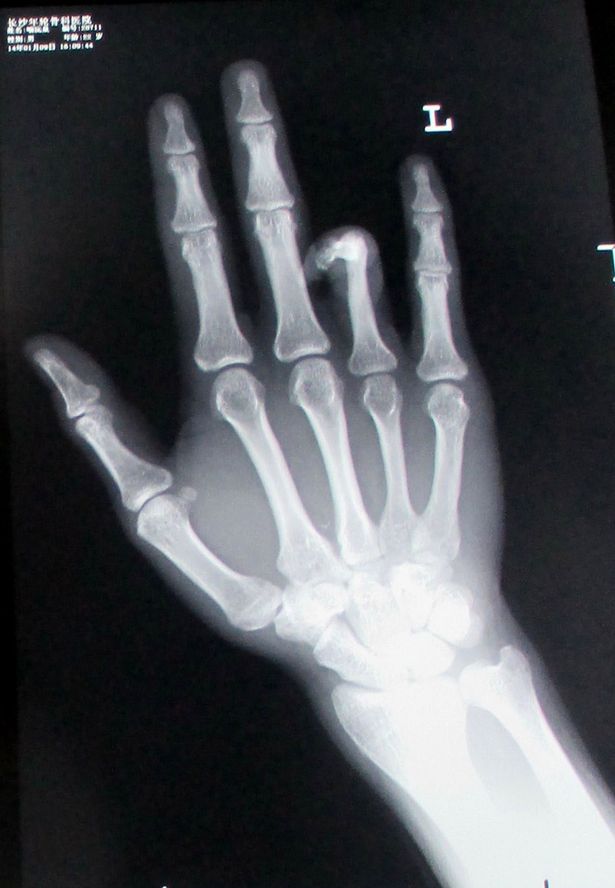

หลังจากตรวจเช็ก เอกซเรย์เรียบร้อยแล้ว ศัลยแพทย์ก็ได้จัดการผ่าตัดเอานิ้วชี้จากเท้าซ้ายของเขา มาต่อเข้ากับนิ้วนางที่กุดไปบนมือข้างซ้าย ซึ่งผลปรากฏว่า ฮา หยวน กลับมามีนิ้วมือครบสมบูรณ์อีกครั้ง และเนียนเสียด้วย แม้ว่าจะต้องแลกกับการทำให้นิ้วเท้ากุดก็ตาม